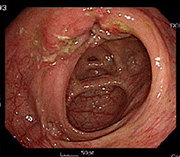

사례 2

치료 전 치료 전 장내 점막 사진